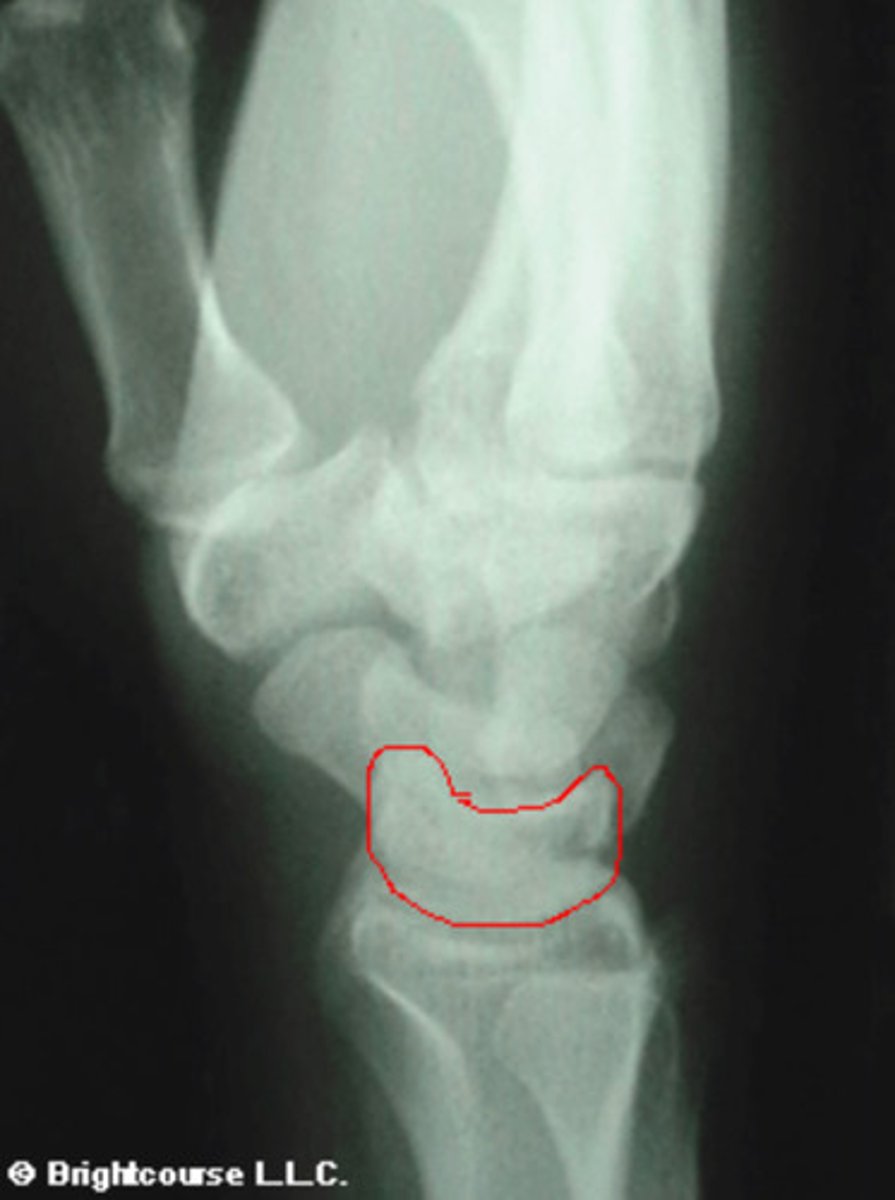

Lunate

What structure is being circled in this image?

3 arcs of carpal alignment

What is being assessed in this image?

Scaphoid

What structure is being outlined in this image?